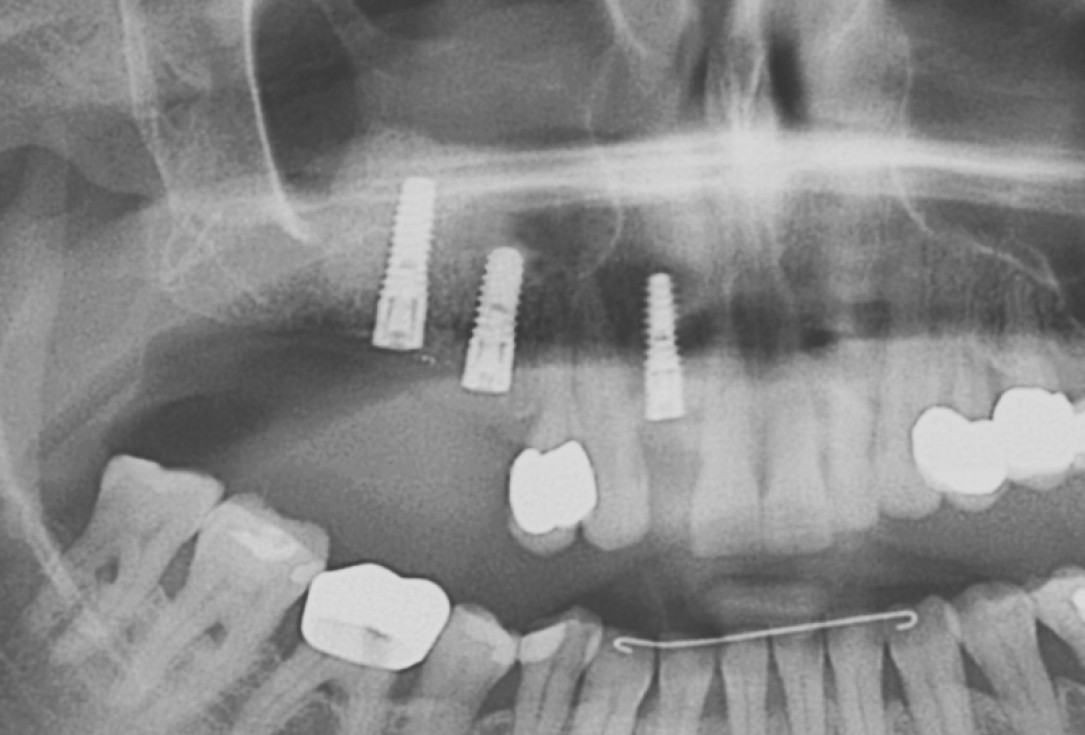

DVT image showing the reduced amount of bone available in the area of the mental foramen